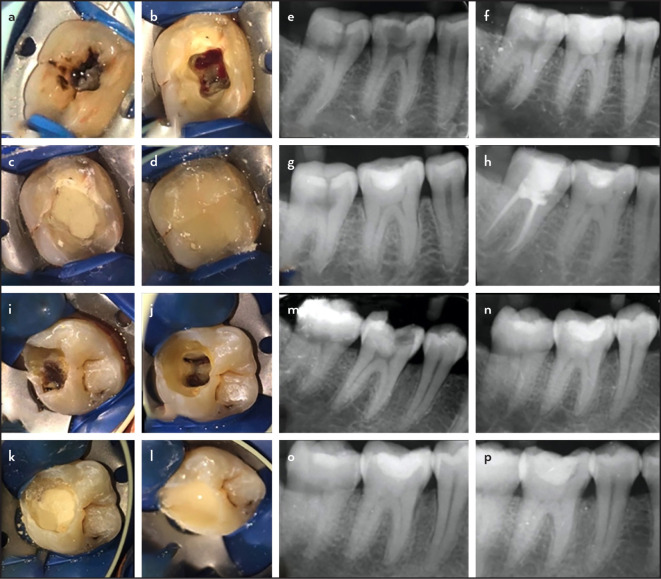

Objective: To evaluate the effect of diode laser (GaAlAs-980 nm) for full coronal pulpotomy (FCP) compared to conventional crown pulpotomy (CCP) in mature teeth with symptomatic irreversible pulpitis (SIP) and assess dentine bridge formation after FCP using CBCT.

Methods: A total of 86 patients (43 per group) with SIP in permanent mandibular molars were included. Access opening and FCP were done, after which haemostasis was achieved with 2.5% NaOCl in the CCP group and a diode laser (GaAlAs-980 nm) in the laser crown pulpotomy group (LCP). Biodentine (Septodont, Saint-Maur-des-Fossés, France) was placed, and the cavity was sealed. Clinical and radiographic follow-ups were done at 6, 12, and 18 months, with additional CBCT evaluation at 18 months. Statistical analysis was performed using the Mann-Whitney U test, and survival rates were assessed using Kaplan-Meier analysis. The Cox proportional model was used to determine the effect of possible covariates on pulpotomy outcomes. P<0.05 was considered to be statistically significant.

Results: The overall success rate for CCP and LCP at 18 months was 88.4% and 93% respectively. At the end of 18 months, 8 cases (5 in CCP, 3 in LCP) failed. The postoperative pain score at 48 hours was significantly higher for CCP (mean +- standard deviation: 1.7+-1.4; p<0.001). CBCT analysis at 18 months revealed thicker dentine bridge formation for LCP (Median & IQR: 0.89, 1.06) compared to CCP (p=0.0479). The Kaplan-Meier curve showed a more rapid decline in the survival rate of CCP (0.89) compared to that of LCP (0.93). Postoperative pain at 48 hours, PAI scores at 6, 12, 18 months, and age were found to affect the hazard ratio based on the Cox regression model.

Conclusion: Within the limitations of this trial, there was no significant difference in the outcome between diode laser and conventional pulpotomy. However, LCP resulted in lesser postoperative pain at 48 hours and thicker dentine bridge formation at 18 months, with a longer estimated survival rate. (EEJ-2023-01-011).